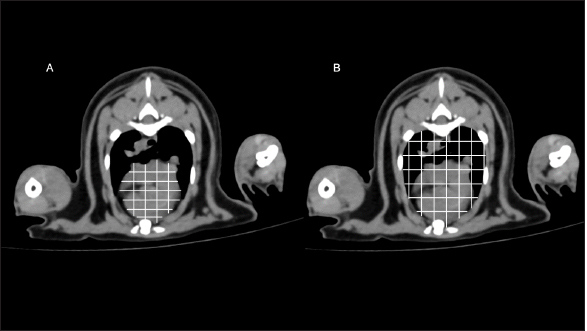

On cross-sectional images at the carina level, thoracic height/width ratio (THW) was determined as described previously (Uehara et al., 2009). A manual drawing using a digital caliper from the ventral border of the vertebrae to the sternum was performed to identify the thoracic height (TH). For the thoracic width (TW), a digital caliper was used from the right to left thoracic wall at the widest part and perpendicular to the TH as shown in Figure 2. THW was then calculated. Relative heart area (RHA) was evaluated by manually drawing the outline of the heart to evaluate the heart area (Fig. 3A). For the thoracic area (Fig. 3B), manual drawing was performed as described previously (Uehara et al., 2009). Finally, RHA was then calculated as the ratio of heart area to thoracic area at the carina level. Transverse vertebral heart score (tVHS) was determined by manual drawing using a digital caliper. Heart height (HH) was the height of the heart and heart width (HW) was the widest distance perpendicular to the HH. The ratio of the sum of HH and HW to the height of the vertebral body at the carina level was then calculated as tVHS (Fig. 4). CT vertebral heart score (ctVHS) was evaluated on the sagittal plane images. The measurement method was performed in the same way as on radiography (Lister and Buchanan, 2000) (Fig. 5). All CT measurements were performed by the same experienced radiologist using the same image archiving PACs system through DICOM viewer software.

Fig. 3. RHA measurement methods. RHA was measured on cross-sectional CT image at the carina level. (A) Heart area was the area of the heart. (B) Thoracic area was the area of the thoracic cavity. RHA was calculated as the ratio of heart area to thoracic area at the carina level. RHA: relative heart area; CT: computed tomography.